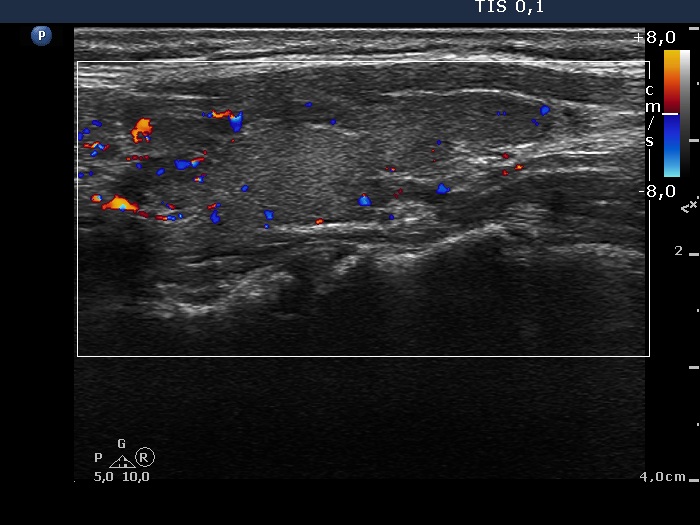

Left lobe, longitudinal scan, color Doppler mode. The vascularization is not specific.